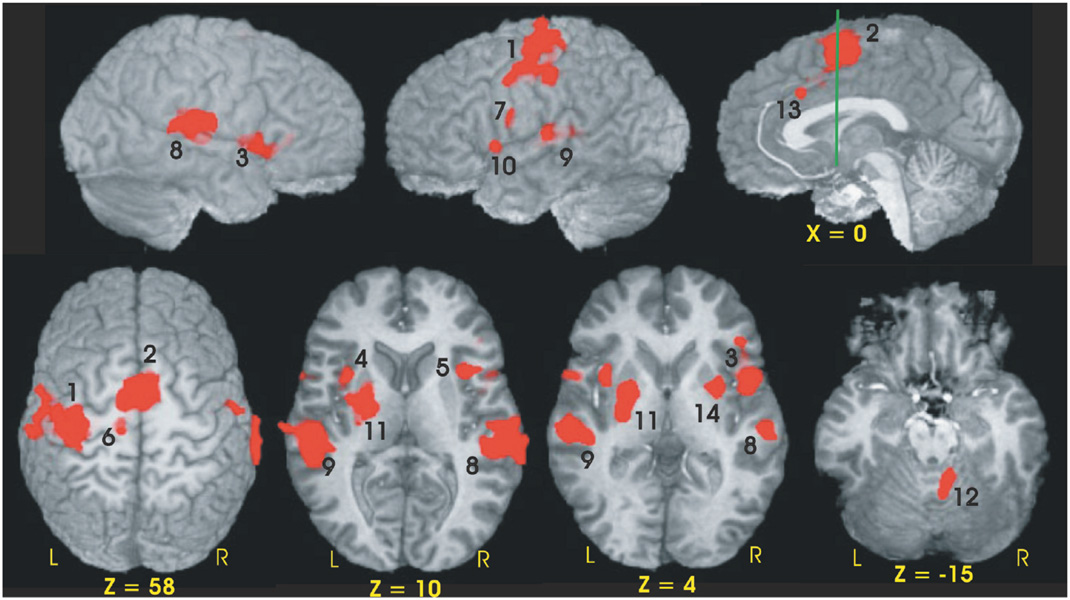

Fourteen functional ROIs were identified from the conjunction analysis performed across the three groups (see Table 3, Fig. 2). Using percent MR signal change as the dependent measure, a 2 (condition) × 3 (group) ANOVA was performed for each fROI. Four of the 14 fROIs demonstrated main effects of condition (S vs. C). As expected from our previous fMRI study of young healthy participants (Rao et al., 1997), fROIs exhibiting greater neural activation during the C condition relative to the S condition included the left sensorimotor cortex (SMC, p = .001) and medial premotor cortex (bilateral SMA/preSMA/CMA, p < .001). Greater activation during the S relative to the C condition was observed in the left and right superior temporal gyri [STG] (p < .001); this was expected since no auditory stimulus was presented during the C condition.

Functional ROIs and volumes of the conjunction mask

Functional ROIs of the conjunction map used to evaluate group differences in MR signal intensity. Numbers adjacent to activation foci correspond to numbers in brackets in Table 3. The green line in the sagittal image (x = 0) is perpendicular to the AC-PC line and is positioned at the anterior commissure (y = 0).

Twelve of the 14 fROIs demonstrated main effects of group. Post hoc analyses revealed 3 distinct patterns of group differences. The first pattern revealed that the CLOSE group had significantly less activation relative to the FAR and CONT groups. This effect was observed in the left anterior insula, right inferior frontal gyrus, bilateral medial premotor area (SMA/preSMA/CMA), and left putamen (see Fig. 3). The second pattern, observed in the right anterior cingulate and right anterior insula, was characterized by a significant stepwise reduction in activation across the three groups (CONT > FAR > CLOSE; see Fig. 4). For the third pattern, the FAR group exhibited significantly increased activation relative to the CLOSE and CONT groups. This effect was observed in the left SMC, left precentral gyrus, left medial frontal gyrus, bilateral STG, and the right cerebellum (see Fig. 5). No significant condition by group interaction effects were observed in any of the 14 fROIs.